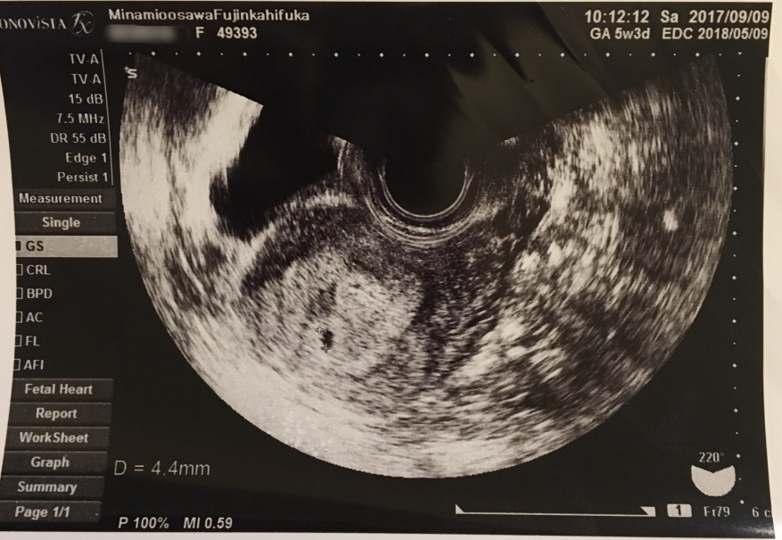

妊娠5週4日 5w4d の超音波 エコー 写真

妊娠5週4日 5w4d の超音波 エコー 写真

第3話 5週4日 卵黄嚢が確認できました 胎嚢の大きくなり方物語 妊娠ぱっぴー

妊娠5週 3 6日 のエコー写真 体験談

5週4日でのエコー写真について教えて下さい 妊娠のq A 解決済み Okwave

5週4日 みんな違ってみんないい

妊娠5週 5w4d で6 3ミリの胎嚢確認 平均よりも胎嚢サイズ小さい むきだしのことば ワーママえむのブログ

胎嚢見えました 妊娠2ヶ月 5週4日 の写真 ベビカム成長記録 妊娠 出産 育児に関する総合情報サイト ベビカム

5週4日目なう Blaue Erde

妊娠5週5日に胎嚢と心音 心拍 を確認 胎嚢と胎芽のエコー写真 画像あり 大きさや形

妊娠5週5日に胎嚢と心音 心拍 を確認 胎嚢と胎芽のエコー写真 画像あり 大きさや形

質問 Itmedia 5週4日でのエコー写真について教えて下さい

エコー写真に詳しい方宜しくお願いします 本日前回生理から計算して5週4 Yahoo 知恵袋